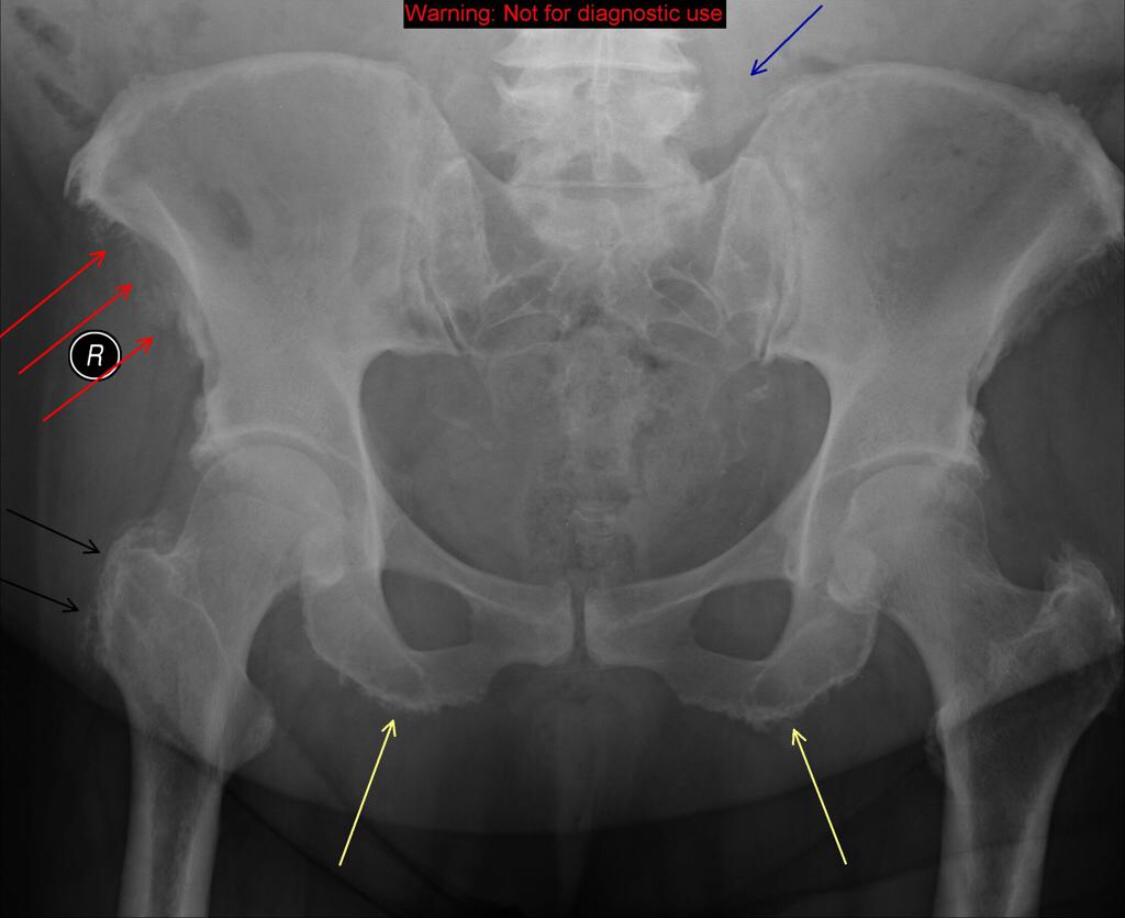

AP radiograph of the pelvis reveals extensive fluffy or "whiskering" enthesopathy of the iliac crests (red arrows), ischial tuberosities (yellow arrows), and the trochanters (black arrows). Note is also made of ossification of the iliolumbar ligament (blue arrow). Importantly, both sacroiliac joints appear normal. These findings are in keeping with diffuse idiopathic skeletal hyperostosis (DISH).

Diffuse Idiopathic skeletal hyperostosis (DISH) is a bone-forming diathesis primarily affecting the spine, with ossification of tendons and ligaments. Most of us are familiar with the spinal findings; however there are extraspinal manifestations as well such as hyperostosis at ligament attachments in the pelvis, calcaneus, tarsal bones, ulnar olecranon and patella.

Usually these are incidental findings without significant morbidity.